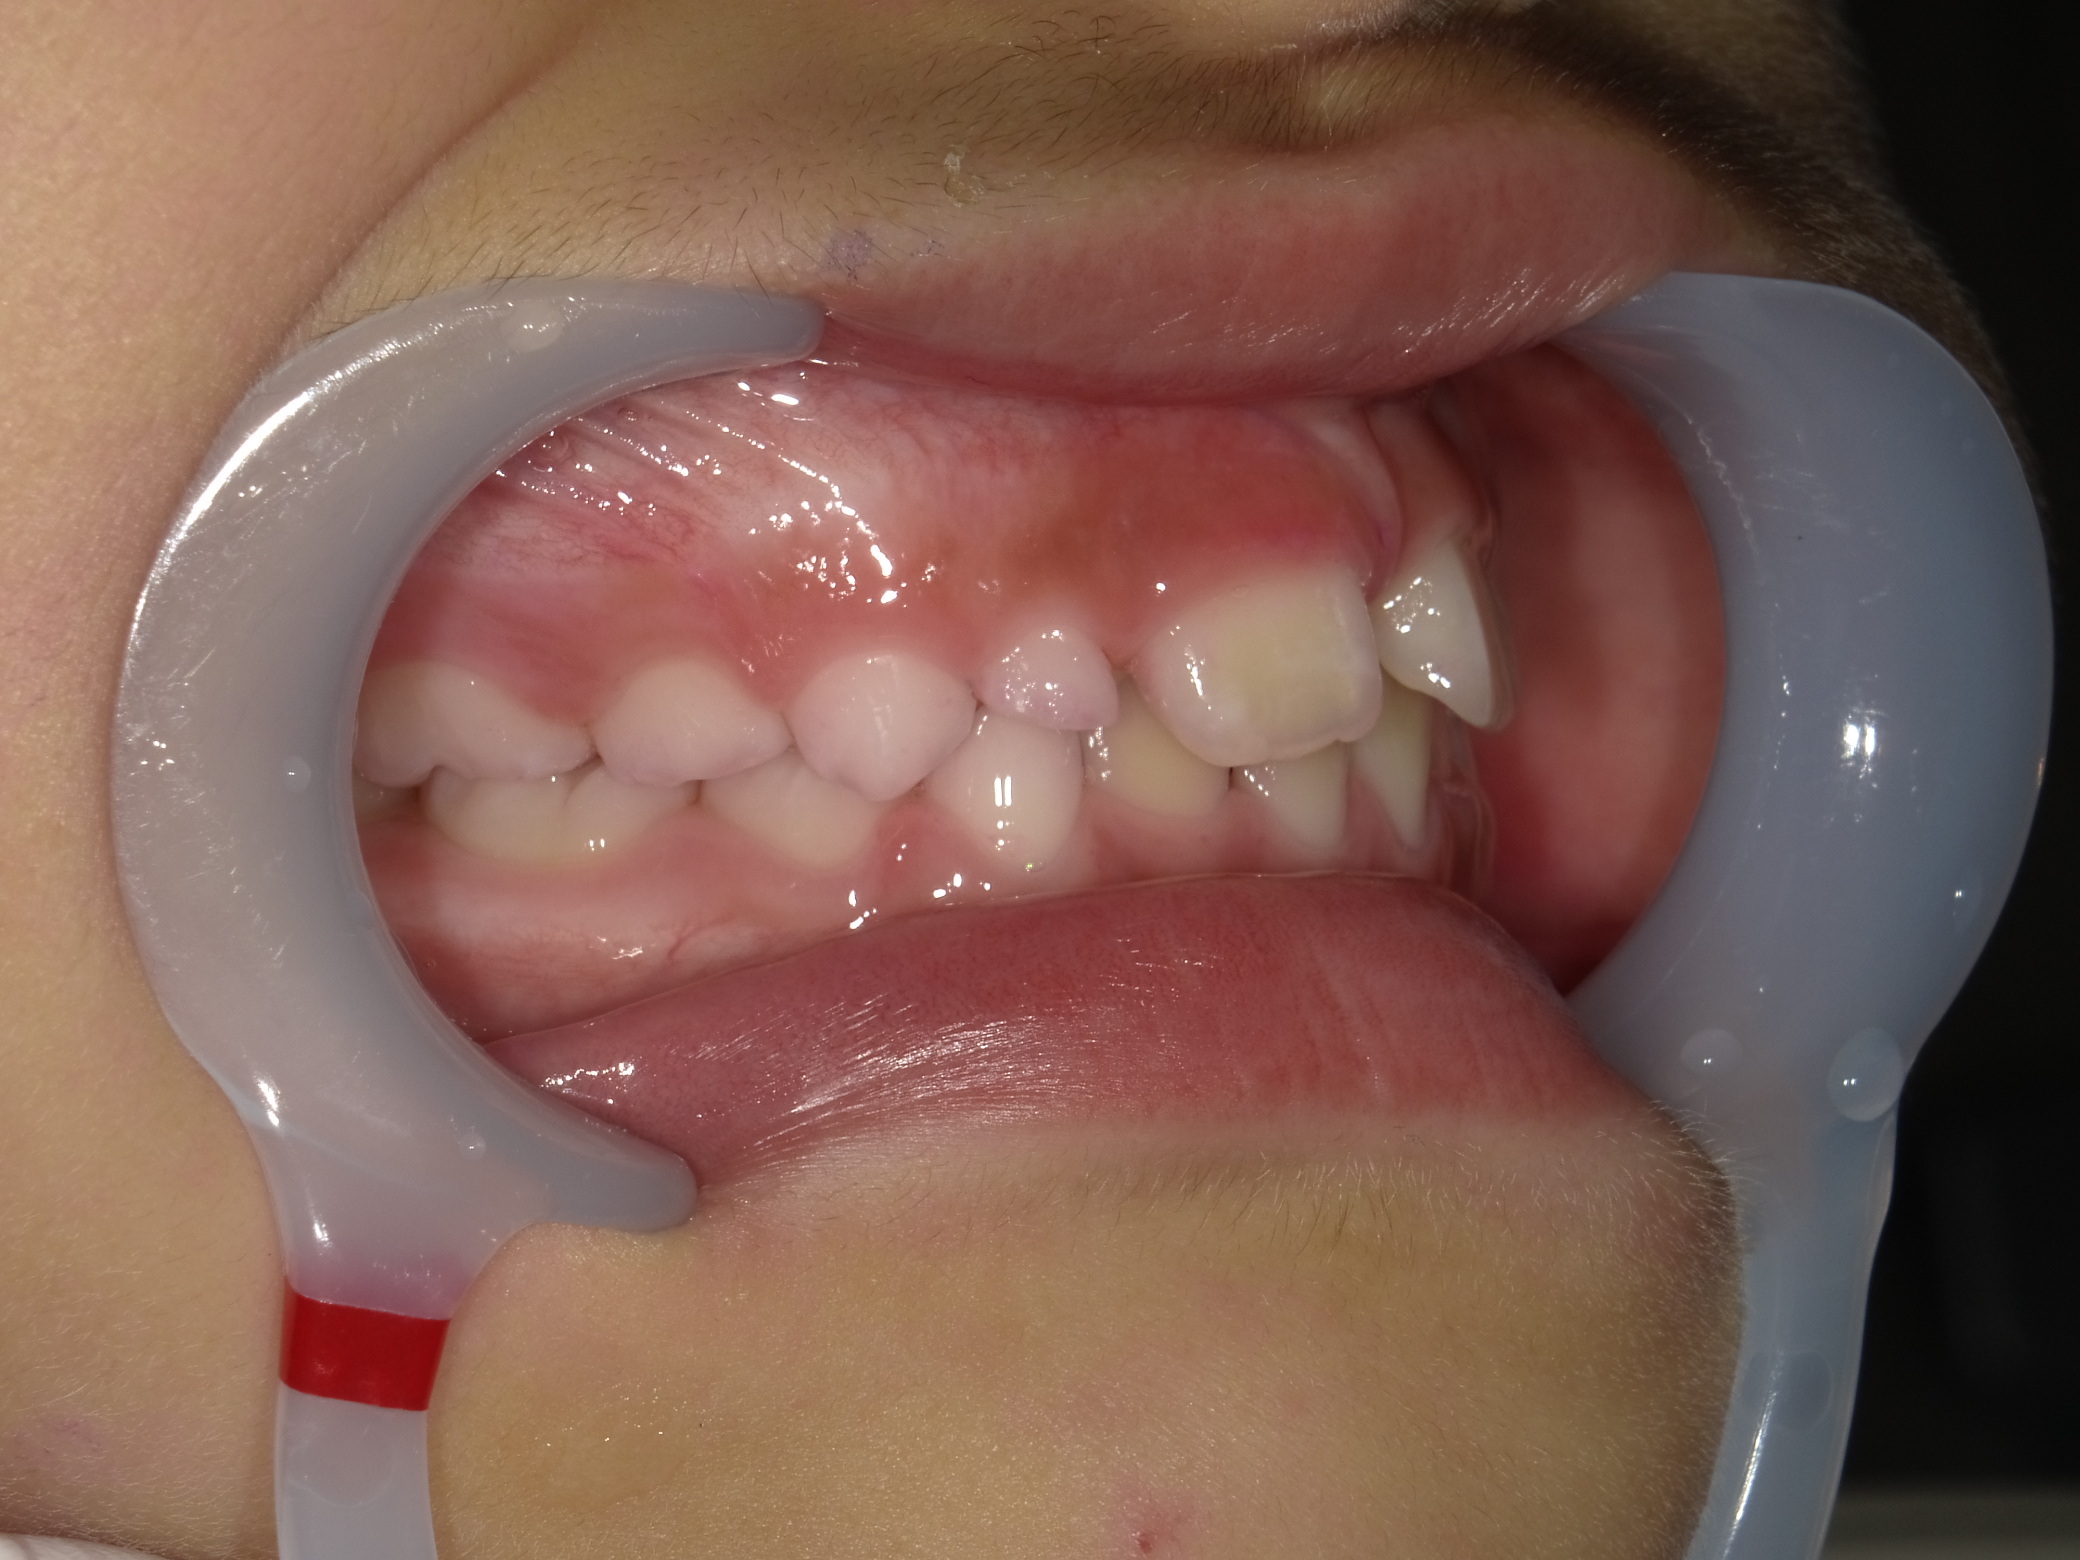

右横